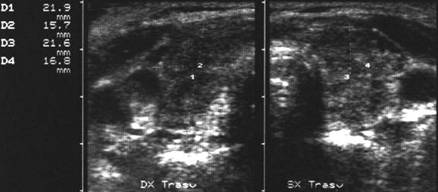

Femeie de 51 ani. Tiroida marita in volume, cu

ecostrutura marcat hipoecogena, neomogenea, cu zone hiperecogene.

Pozitivitatea ridicata a titlului de anticorpi antitireoglobulina si antiperoxidaza.

Cresterea TSH ca in hipotiroidism

subclinic.

Femeie de 51 ani. De multi ani cu terapie sustitutiva cu tiroxina pentru hipotiroidism primar cu tiroidita Hashimoto. Tiroida moderat marit in volum, cu ecostrutura tipica de atingere cronica, cu contur difuz, rau delimitabil, structura grosolana, cu alternanta de arii hipoecogene, cu alele ecogene si striuri de fibroza.

Aceeasi pacienta. La doppler color si powercolordoppler – crestere marcata a vascularizatiei glandei.